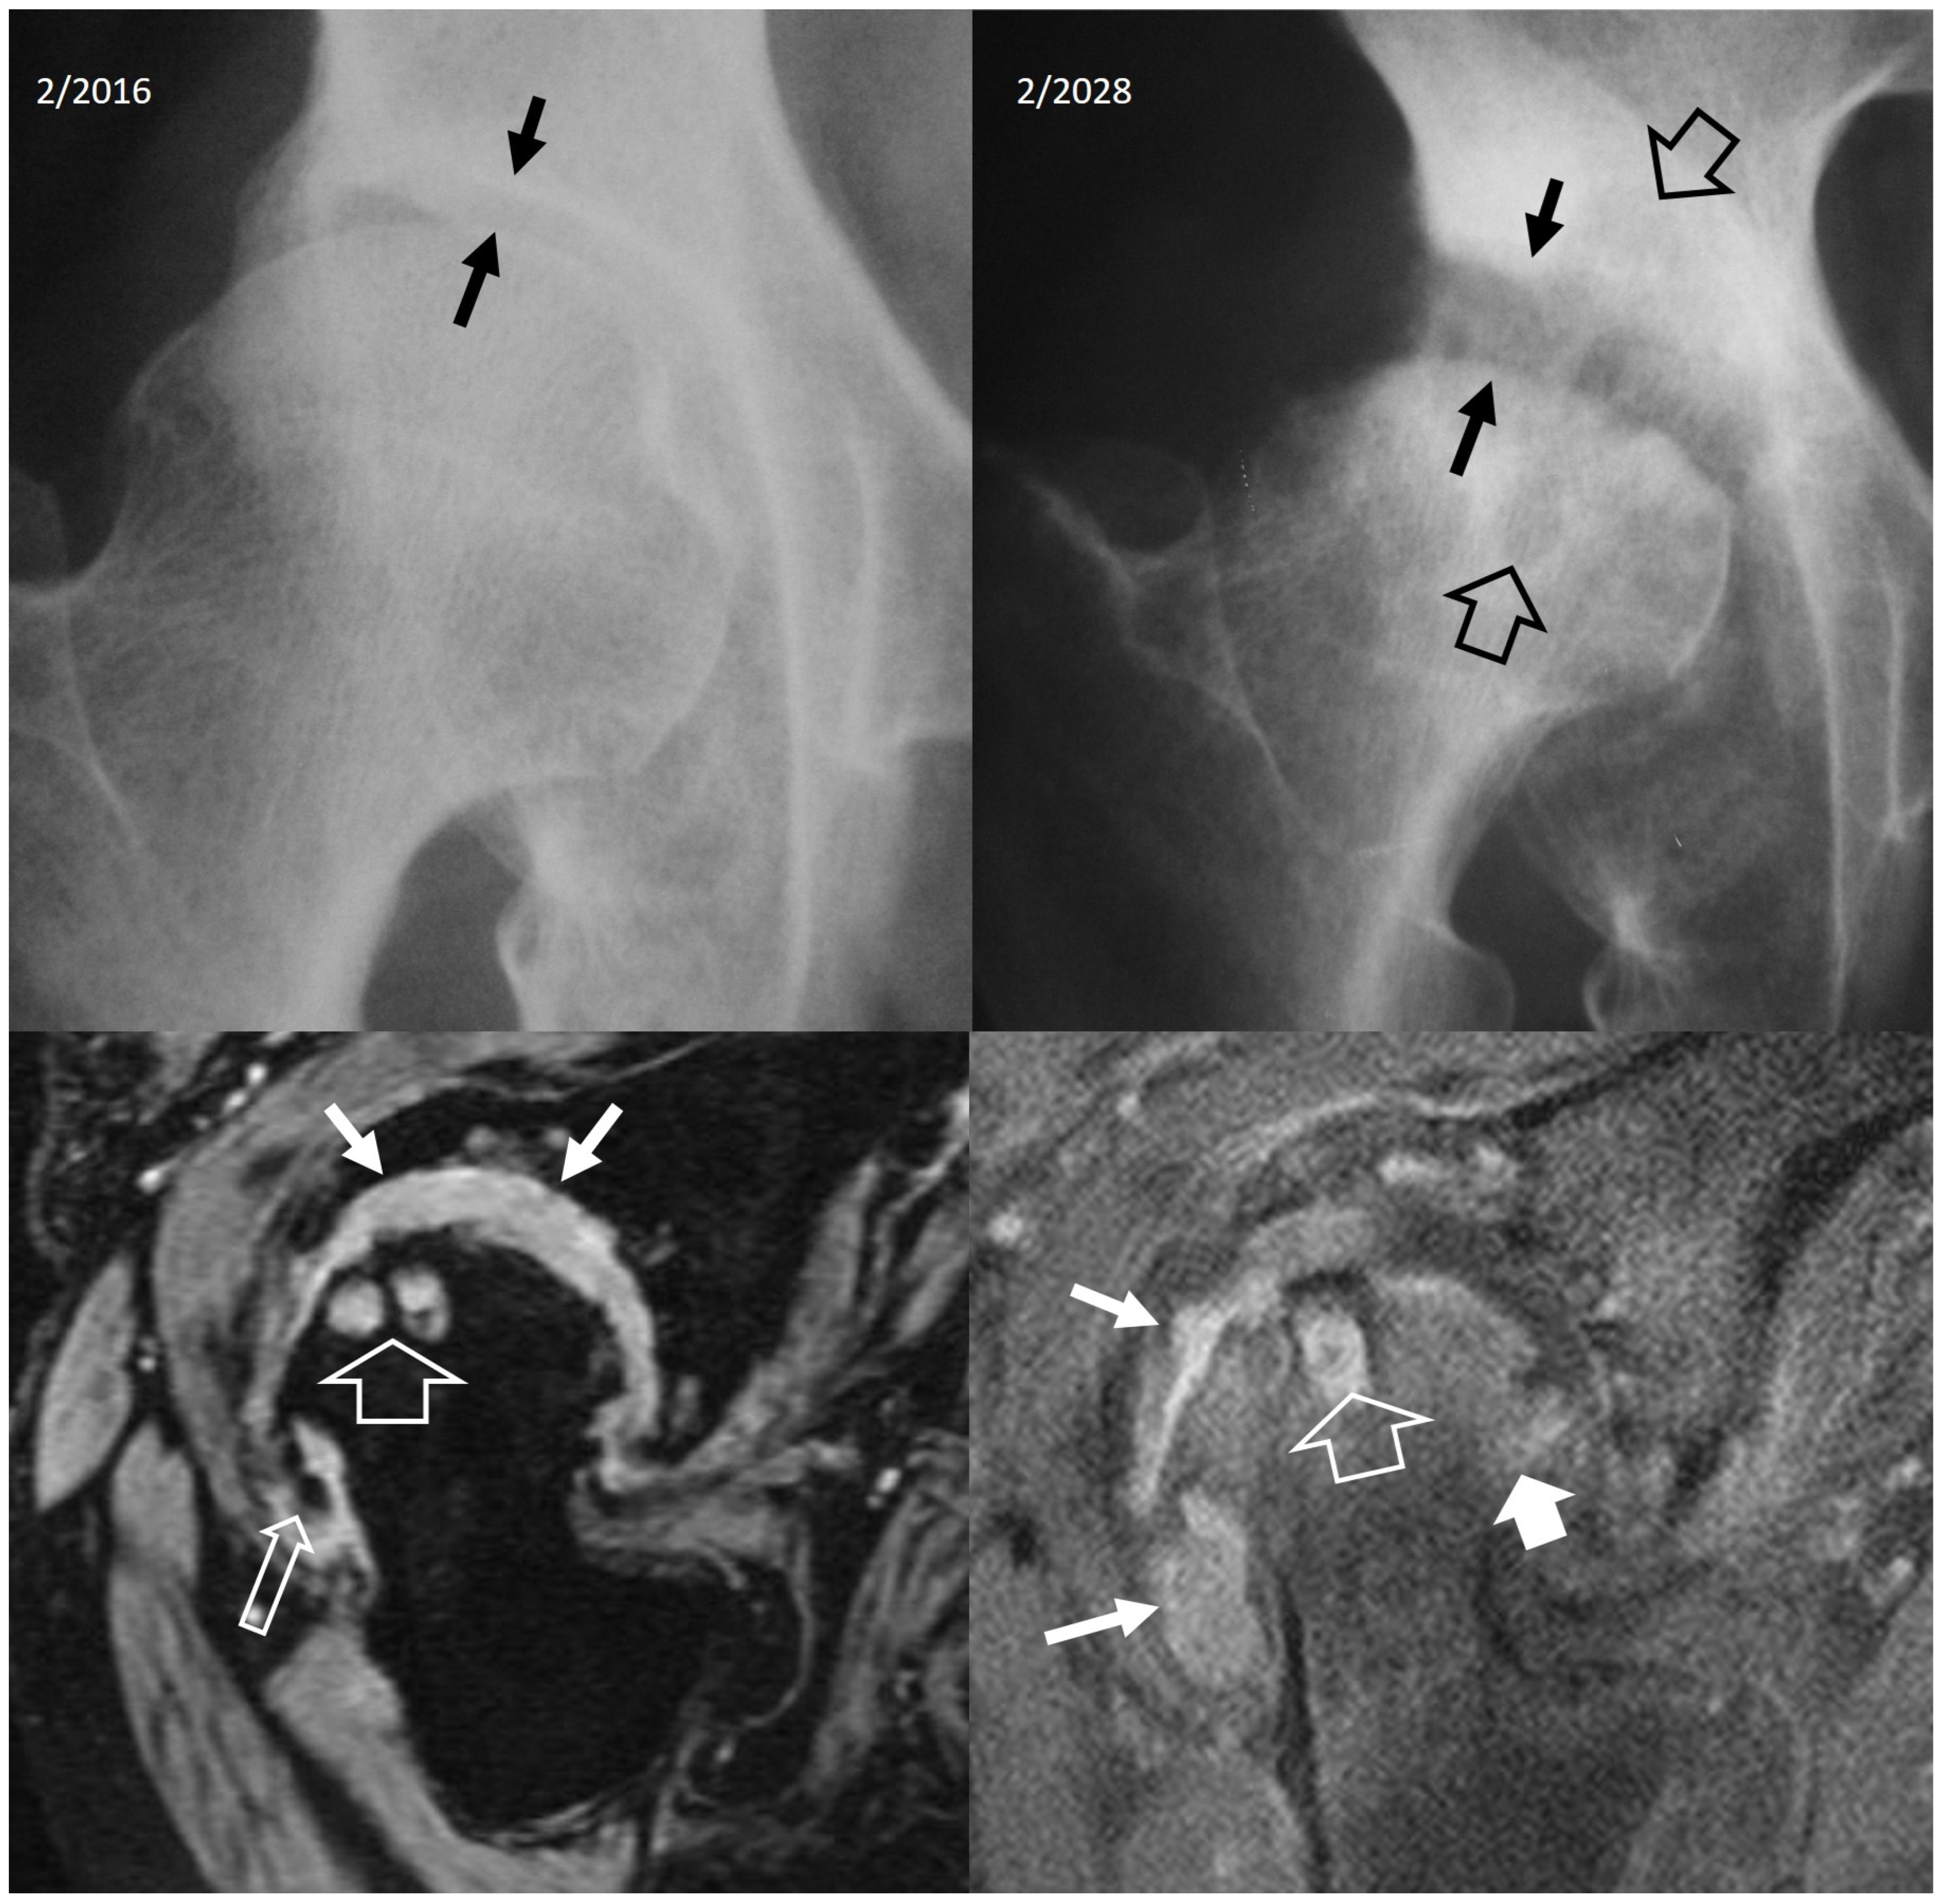

4.2.4. Rapidly Destructive Osteoarthritis of the Hip

4.2.5. Neoplasms